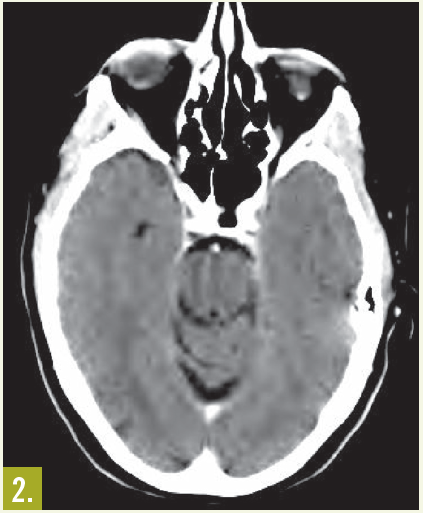

Physical examination. The patient had moderate proptosis; extraocular motions of the left eye were restricted in all directions. She had no lymphadenopathy. Oropharynx was visually unremarkable; however, fiberoptic nasopharyngoscopy revealed a posterior superior nasal cavity mass. A contrast CT scan of the head showed a large mass lesion at the level of the ethmoid sinus, eroding into the left orbit and displacing the left globe (Figure 1).

MRI of the head showed a 5.3 cm x 4.2 cm x 4.2 cm enhancing mass at the base of the brain that extended into the nasal cavity, with erosion into the cribriform plate, ethmoid sinuses, and planum sphenoidale.

Results of an ethmoid sinus mass biopsy confirmed high-grade diffuse large B-cell lymphoma. Staging CT scans showed no metastatic disease, and cerebrospinal fluid analysis revealed no malignant cells. A bone marrow biopsy specimen showed no evidence of light chain monoclonality, no overt evidence of B-cell lymphoproliferative disorder on flow cytometry analysis, and no lymphoma. This was consistent with stage IAE disease.

Outcome of the case. In this patient, treatment with rituximab, cyclophosphamide, doxorubicin, vincristine, and prednisone chemotherapy for 6 cycles resulted in excellent clinical and radiological response (Figure 2).